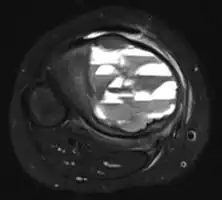

| Aneurysmal bone cyst (fibula, around knee). | |

X-ray and CT scan show lytic expansion lesions with clear borders.[1] Expansion of cortex gives the lesion a balloon-like appearance. Larger lesions may appear septated.[10] MRI reveals fluid levels.[1] Bone scan shows outer radiotracer uptake, with a central dark area.[1]

X-ray: ABC large long bone of lower leg near knee

MRI scan: showing fluid levels